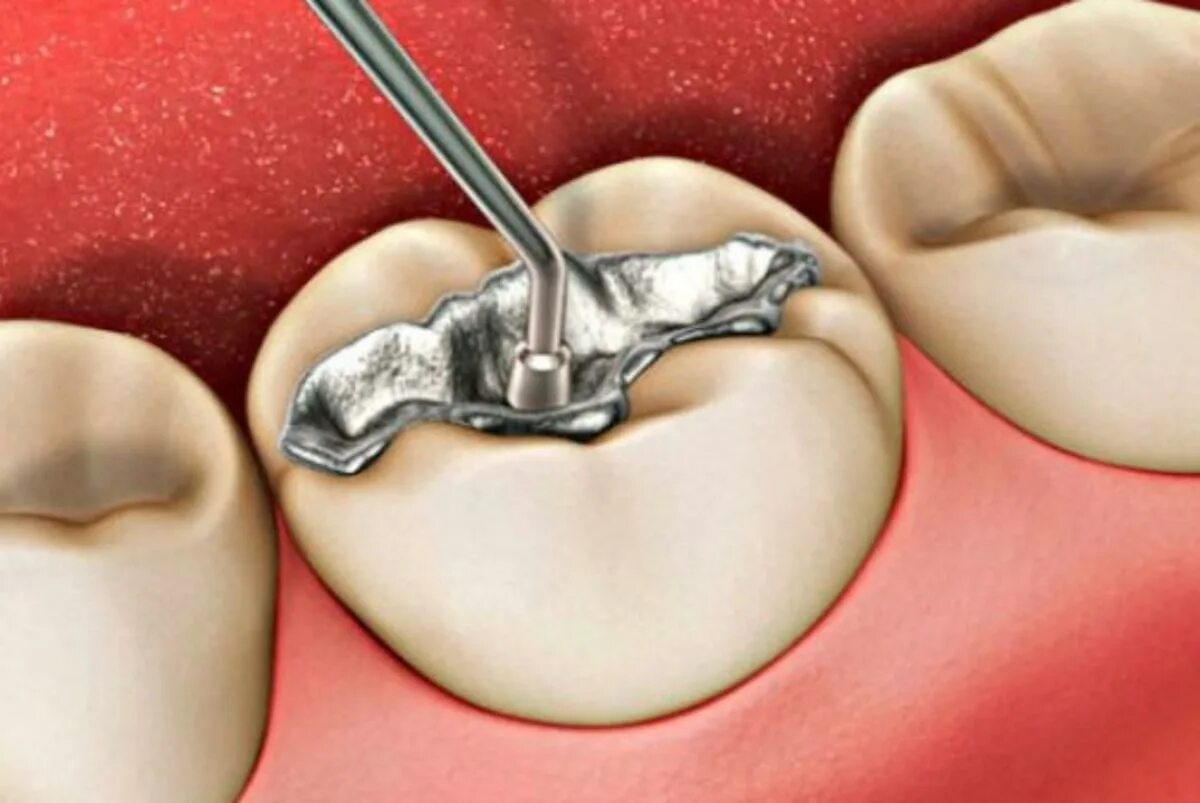

Входит в амальгаму